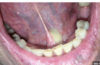

A 21-year-old man presents with halitosis and mouth pain. Examination reveals very poor dental hygiene with bleeding gums and widespread gingival ulceration. He has a temperature of 38.0ºC. You advise him to see a dentist. What other treatment options should be offered?

The correct answer is Paracetamol + oral metronidazole + chlorhexidine mouthwash.

This combination provides optimal management for acute necrotising ulcerative gingivitis (ANUG), also known as Vincent’s angina. ANUG is caused by a fusospirochaetal infection, primarily involving Fusobacterium nucleatum and Treponema vincentii. Metronidazole is the antibiotic of choice as it is effective against anaerobic bacteria. Chlorhexidine mouthwash helps reduce bacterial load and promotes healing, while paracetamol addresses pain and fever.